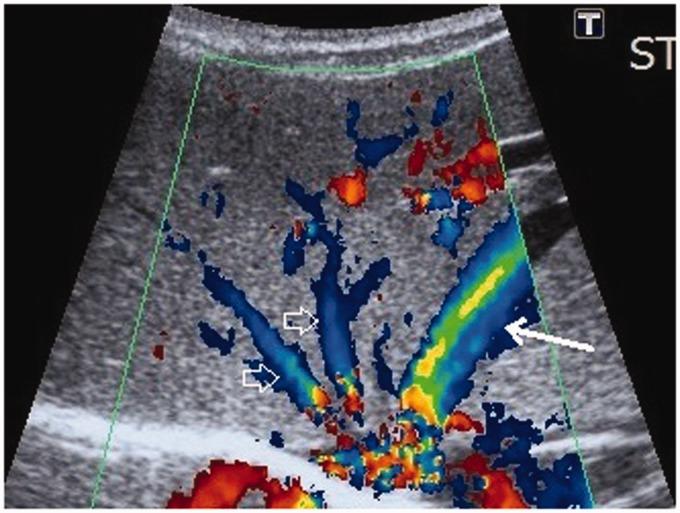

Intrahepatic congenital portosystemic venous shunts are rare vascular anomalies. We report a unique case of a neonate with an intrahepatic congenital portosystemic venous shunt with concurrent congenital duodenal web. Such association has not been previously reported to our knowledge. Interestingly, the shunt became apparent on the seventh day, after a delayed start of oral feeding due to the neonate's recovery from the duodenal web surgery. The shunt was small and the clinical symptomatology mild. No direct treatment was required. The laboratory and the ultrasound follow-up of the child noted a spontaneous resolution of the shunt by the age of six months.

肝内先天性门体静脉分流是罕见的血管异常。我们报告了一例独特的新生儿病例,该新生儿患有肝内先天性门体静脉分流并伴有先天性十二指肠蹼。据我们所知,此前尚未有这种关联的报道。有趣的是,由于新生儿从十二指肠蹼手术中恢复,经口喂养开始延迟,分流在第七天变得明显。分流较小,临床症状轻微。无需直接治疗。对该患儿的实验室检查和超声随访发现,分流在六个月大时自行消退。